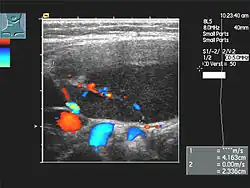

Linfadenopatía en un Golden Retriiever de 12 años de edad. El ganglio inflamado es uno submandibular diagnosticado con linfoma. | ||